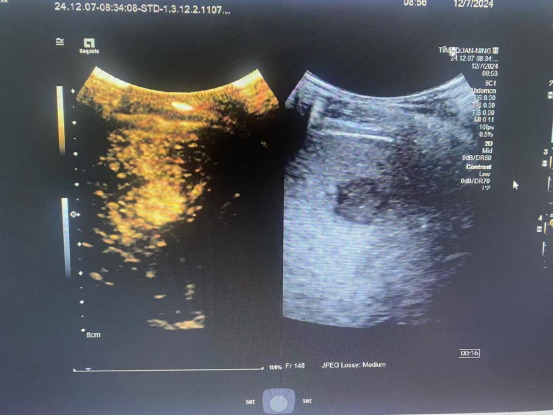

传统超声虽常用,但对微小病变或复杂情况可能误诊。肝脏超声造影则大不同,注入微泡造影剂后,肝脏内部血管与组织在动脉期、门静脉期、延迟期的细微变化尽显于超声图像之上。肿瘤踪迹无所遁形,良恶性轻松初判,炎症、纤维化程度也能精准度量。